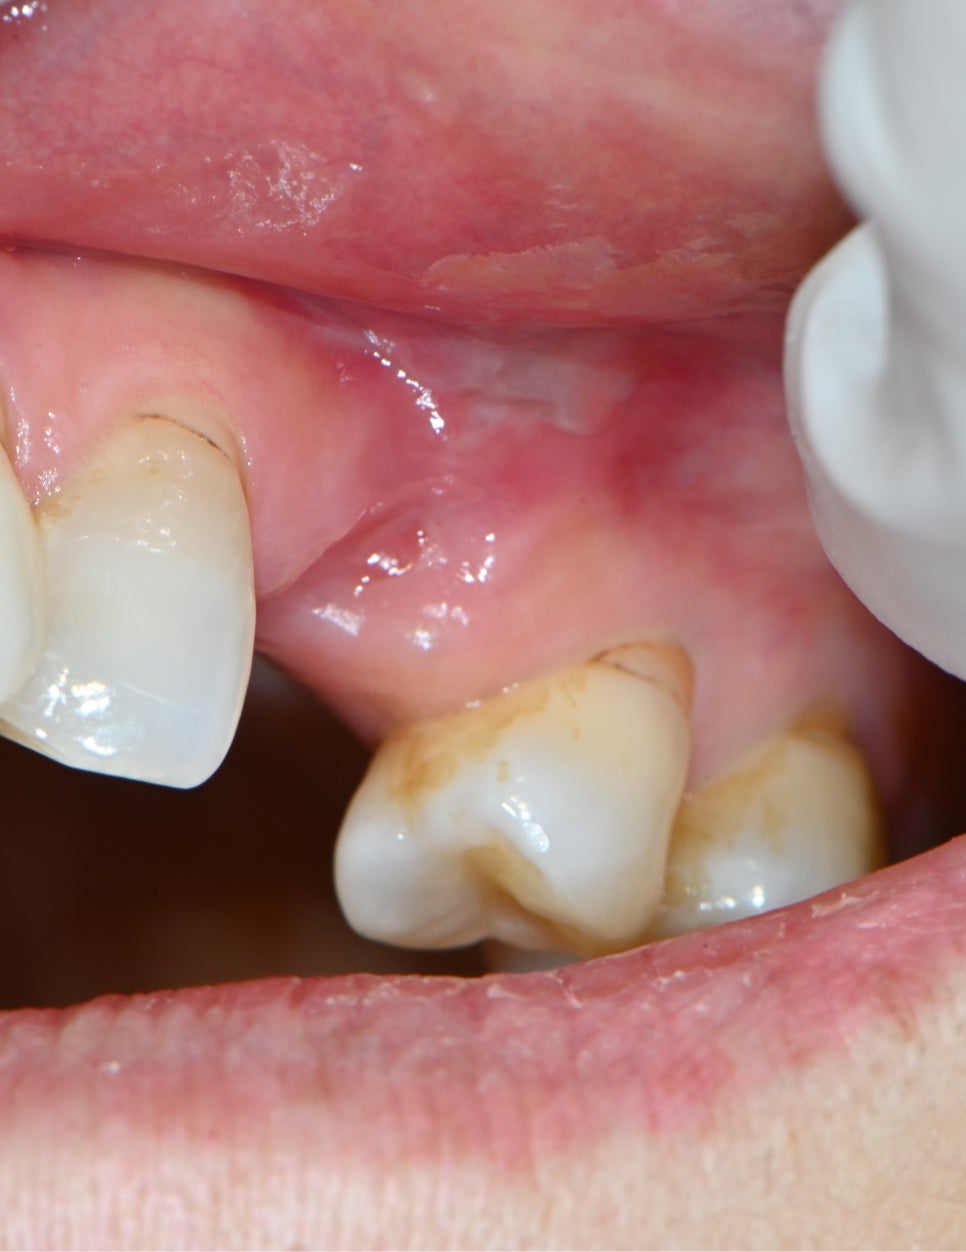

📸 경과 사진

골수염(Osteomyelitis) 제거 후 사진

우선 염증을 부분적으로 제거하고 약물치료를 진행하며 경과를 관찰했어요.

잇몸 붓기와 고름이 점점 줄어들었고,

📸 제거된 염증 조직

골수염(Osteomyelitis) 염증 조직 제거 사진